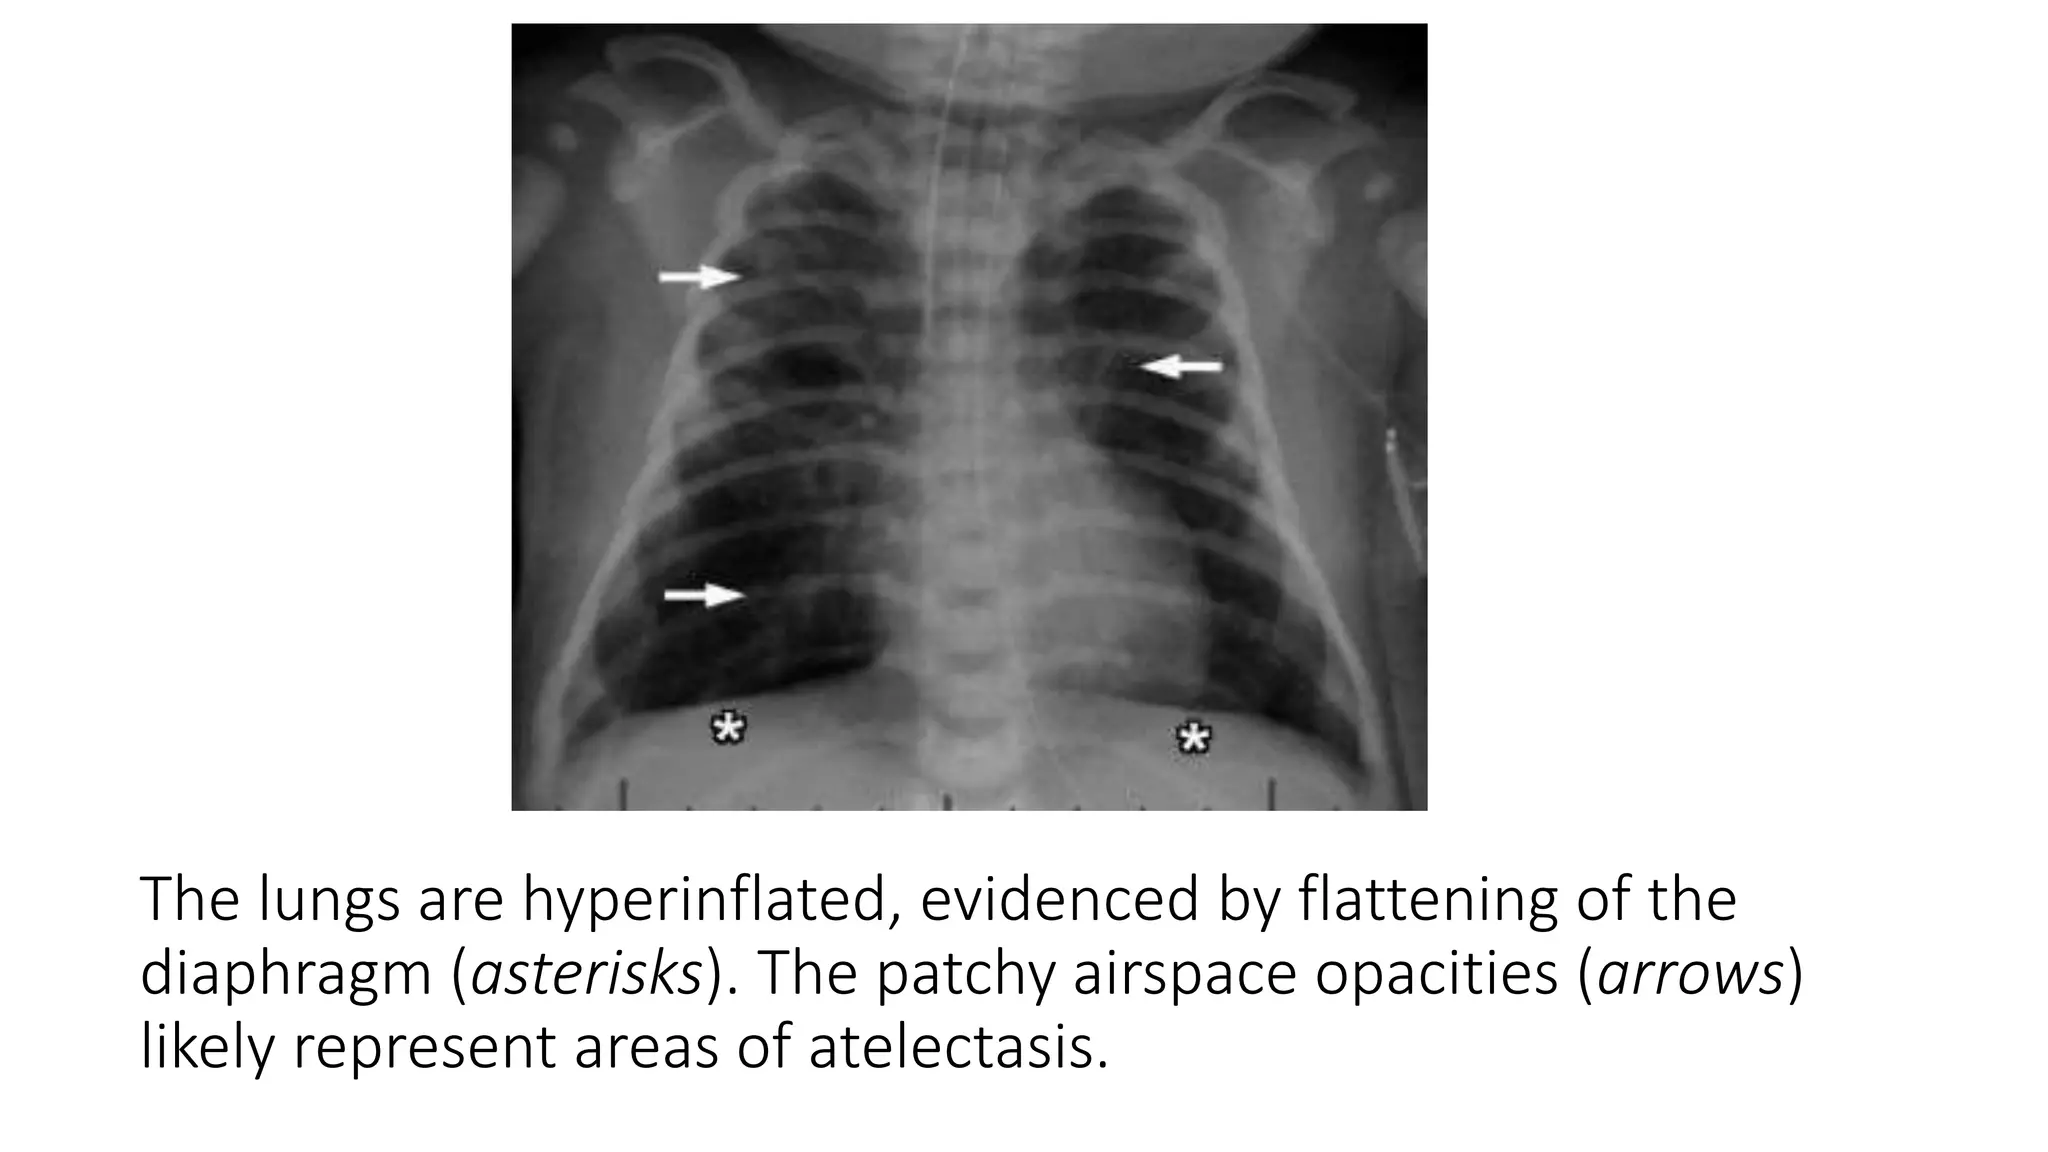

This document provides an overview of neonatal chest x-rays, including when they should and should not be performed, what a normal x-ray looks like, common positions of tubes and catheters, and common causes of respiratory distress in neonates. It discusses the appearance of a normal chest x-ray as well as conditions like respiratory distress syndrome, transient tachypnea of the newborn, meconium aspiration syndrome, and pneumonia. Surgical conditions like diaphragmatic hernia and esophageal atresia are also reviewed.